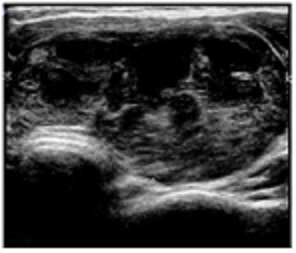

Overlying skin was normal and surface was smooth. There was no associated lymphadenopathy or dyshormonogenesis. Clinically a diagnosis of diffuse goiter was made in a euthyroid patient. Investigations revealed a normal hemogram and chest radiograph.T3,T4, thyroid stimulating hormone (TSH) and thyroid peroxidase (TPO) levels were normal. Ultrasonography revealed enlarged lobes, right lobe measuring 7.6x2.4x2.3cms, left lobe measuring 3.6x1.6x1.4 cms. The entire thyroid gland appeared heterogeneous with multiple hypoechoic cystic areas and internal septations, suggestive of thyroid abscess (Figure 2)

Figure 2: USG of thyroid showing herterogenous thyroid gland with multiple hypoechoic cystic areas and internal septations.